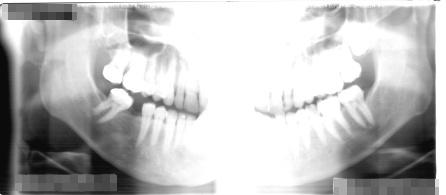

Filme Radiográfico Panorâmico

O filme panorâmico proporciona uma visão abrangente das arcadas dentárias, ossos maxilares e estruturas adjacentes.

É amplamente utilizado para avaliação inicial de pacientes, planejamento ortodôntico, identificação de terceiros molares inclusos e acompanhamento de fraturas mandibulares.